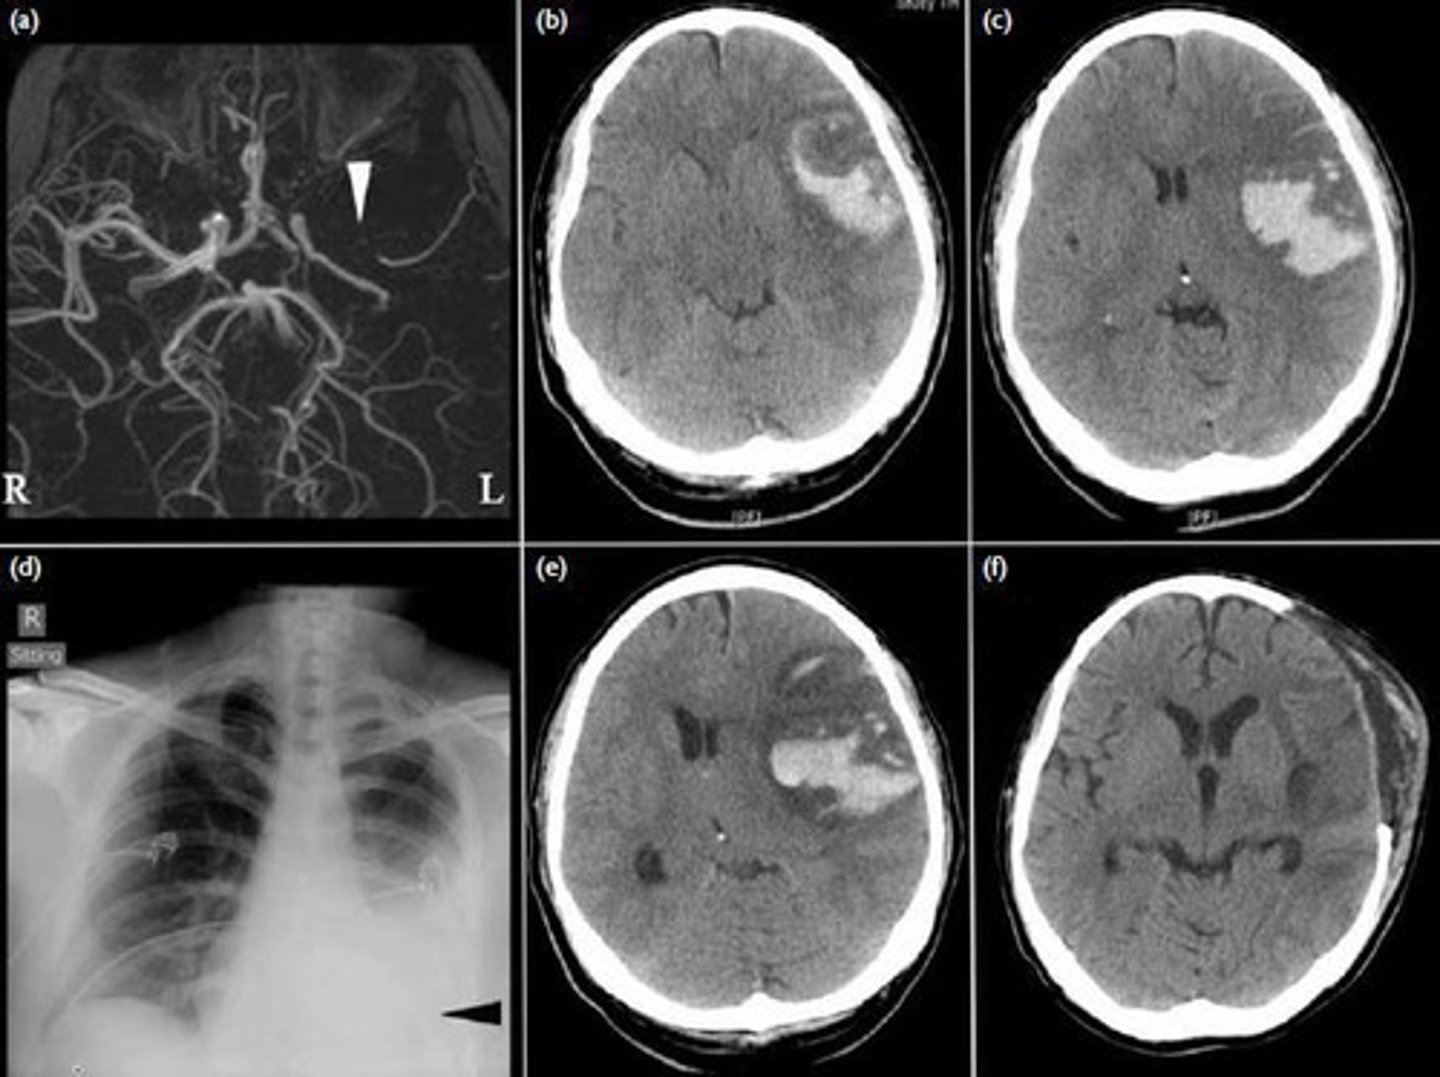

What is a hemorrhagic stroke?

A stroke caused by the rupture of a cerebral blood vessel.

What is an obstructive stroke?

A stroke caused by the occlusion or blockage of a blood vessel.